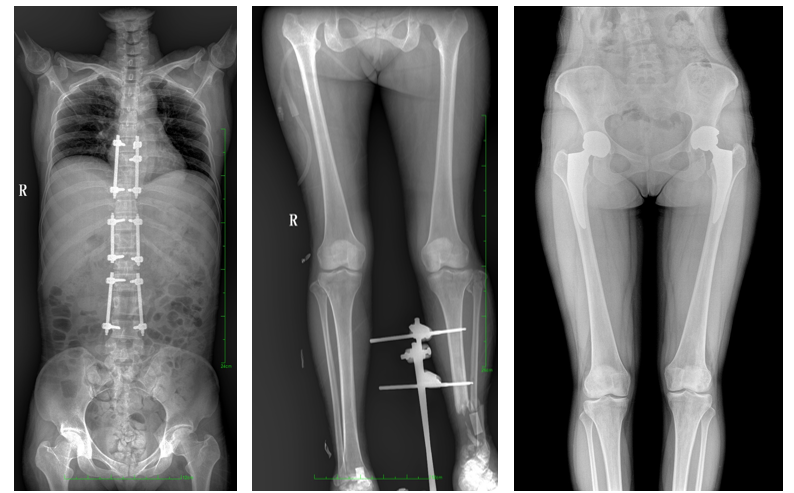

一、成像面積大。17"*34"有效視野,一次成像不拼接。相較于多張攝影再軟件拼接的DR設備,大視野平板動態(tài)DR解決了拼接圖像存在密度不均勻,拼接處圖像配準和放大效應等問題,給臨床帶來了大視野影像解決方案,可一次性覆蓋全脊柱或雙下肢影像。

如:全脊柱狀態(tài)評估、長骨關(guān)節(jié)活動度、下肢靜脈造影瓣膜功能評估、消化道功能評估、脊髓造影等更多大視野臨床應用,多面手給醫(yī)生更多驚喜。

PLX8600大視野平板動態(tài)DR可在低輻射劑量下獲得患者站立位、臥位的高質(zhì)量影像。搭載自主研發(fā)的圖像均衡處理系統(tǒng),能夠很好的均衡人體不同厚度組織的影像,視野大,圖像清晰,層次豐富。